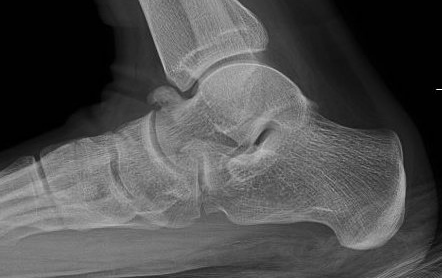

Xray

| Talar beaking | C Sign | Harris axial view | Ball and socket ankle joint |

|---|---|---|---|

| Traction spur due to increased stress | Medial outline talar dome and posterior sustenaculum tali |

40 degree axial view Ski jump view Visualize middle facet |

Secondary to rigid subtalar joint Develops to allow inversion / eversion |

Talar beaking with C sign